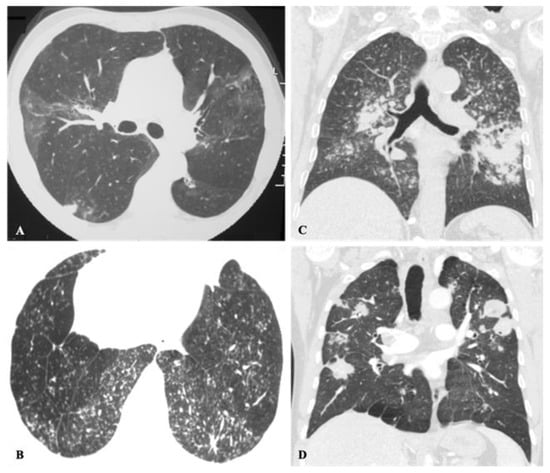

2.5. Mixed Pattern

| Lung Nodule or Mass | Non-Resolving Pneumonia | Chronic Cavitating Disease | Disseminated Infection | Bronchiectasis & Asthma | |||||

| Imaging Clue | Dx | Imaging Clue | Dx | Imaging Clue | Dx | Imaging Clue | Dx | Imaging Clue | Dx |

| Adenopathy | Coccidioidomycosis Histoplasmosis | Consolidation + large nodules/masses | Blastomycosis Cryptococcosis Paracoccidioidomycosis | Grape-skin cavities + Lymphadenopathy | Coccidioidomycosis | Miliary ARDS Extrathoracic | ++ Histoplasmosis Coccidioidomycosis | High-attenuation mucus plugging Finger in glove | ABPA |

| Lung Mass | Cryptococcosis Blastomycosis | Adenopathy | Coccidioidomycosis Histoplasmosis | Calcified nodes | Histoplasmosis | ||||